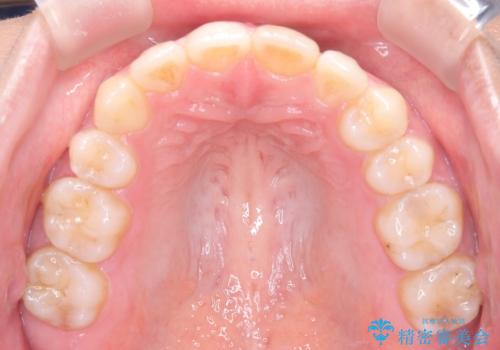

矯正後の後戻り インビザラインで改善

- 7ヶ月

前歯のガタツキを改善する治療法として、マウスピース矯正が適していることが多いです。

マウスピース矯正は、金属製のブラケットやワイヤーを使用せずに、透明なマウスピースを装着して歯を移動させる方法です。そのため、目立たず、痛みも少ないです。